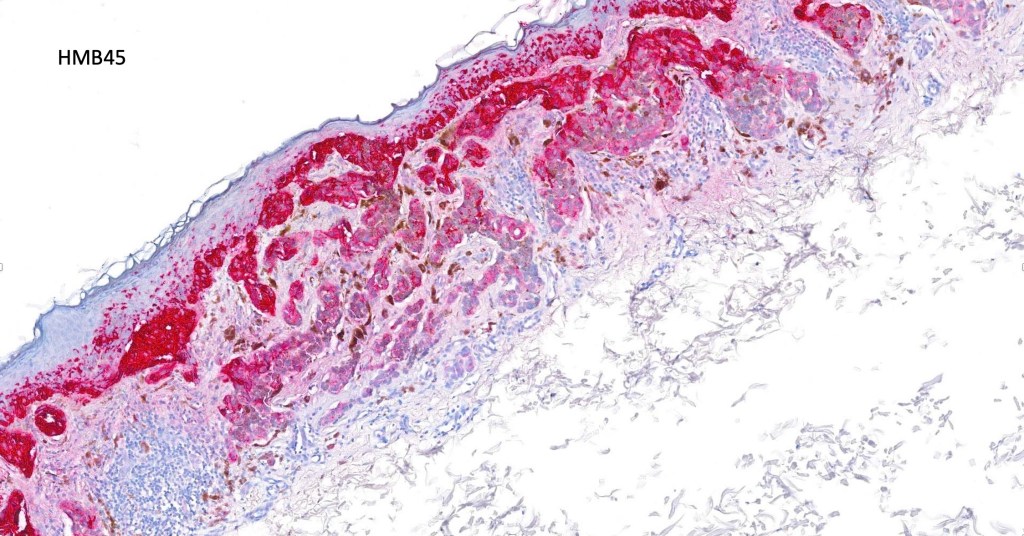

. HMB45 shows gradation with depth, Ki67 is low